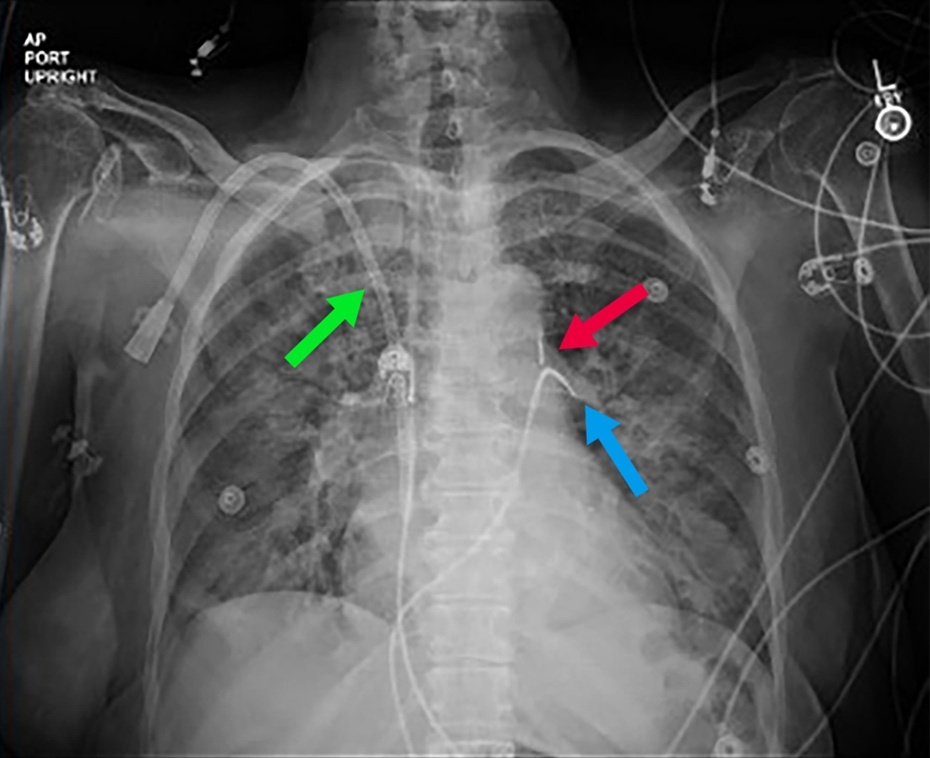

Urgent coronary angiography showed severe 3-vessel disease with 80% to 90% ostial left main and mid-left anterior descending stenosis. The left ventricular end-diastolic pressure was 20 mm Hg. A 40-cc intra-aortic balloon pump (IABP) was placed for hemodynamic support (Figure 1) and percutaneous coronary intervention was performed. Hypotension and vasopressor requirement persisted despite counterpulsation. The indirect Fick cardiac index was 3.6 L/min/m2 with a calculated systemic vascular resistance of 593 dyne-sec-cm-5. Close inspection of the arterial pressure tracing showed an unusually low assisted end-diastolic pressure of 29 mm Hg with substantial improvement when counterpulsation was paused (Figure 2). Echocardiography confirmed normal biventricular systolic function and excluded pericardial effusion and aortic regurgitation. Liver imaging and cortisol level were normal, and a bedside arteriovenous fistula occlusion test did not result in an increase in blood pressure.

Empiric antibiotics were initiated. Subsequently, blood cultures returned positive for Staphylococcus aureus, and the dialysis catheter was removed. Because counterpulsation was hemodynamically counterproductive by worsening hypotension, the IABP was removed, and vasopressor requirements diminished. Further investigation into persistently positive blood cultures revealed likely septic thrombophlebitis involving the right-sided central veins (internal jugular, subclavian, superior vena cava) in addition to aortic root abscess, L1-L5 osteomyelitis with epidural phlegmon, and psoas muscle abscess.